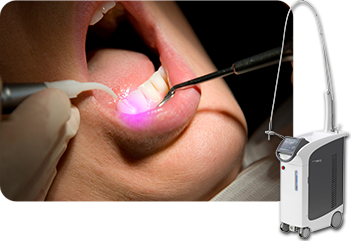

当院では「アーウィンアドベールEVO」を導入し、保険診療にてう蝕、切開、口内炎治療等のレーザー治療が可能になりました。

歯ぐきの黒ずみにレーザーを照射することで、メラニン色素を除去し、明るいお色味の歯ぐきを取り戻すことができます。当院では痛みと振動が少なく、身体にもやさしいレーザー「アーウィンアドベールEVO」で施術を行います。

| レーザー照射による メラニン色素除去 |

片顎 5,000円(税込) |

|---|